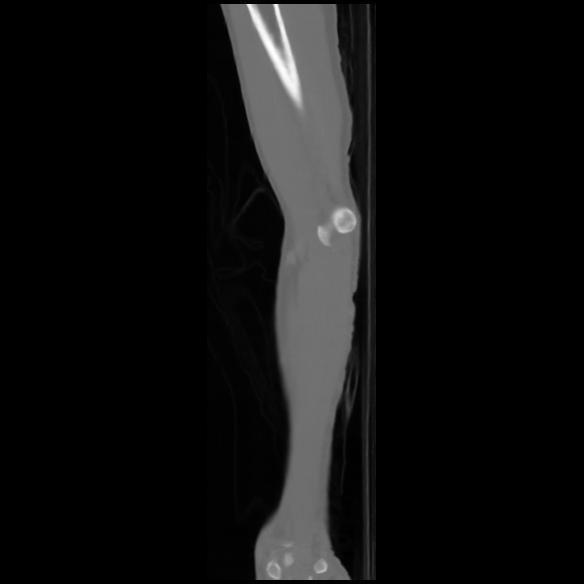

7 CUERPO,CE,Sagittal,3.000,CUERPO,Sagittal,